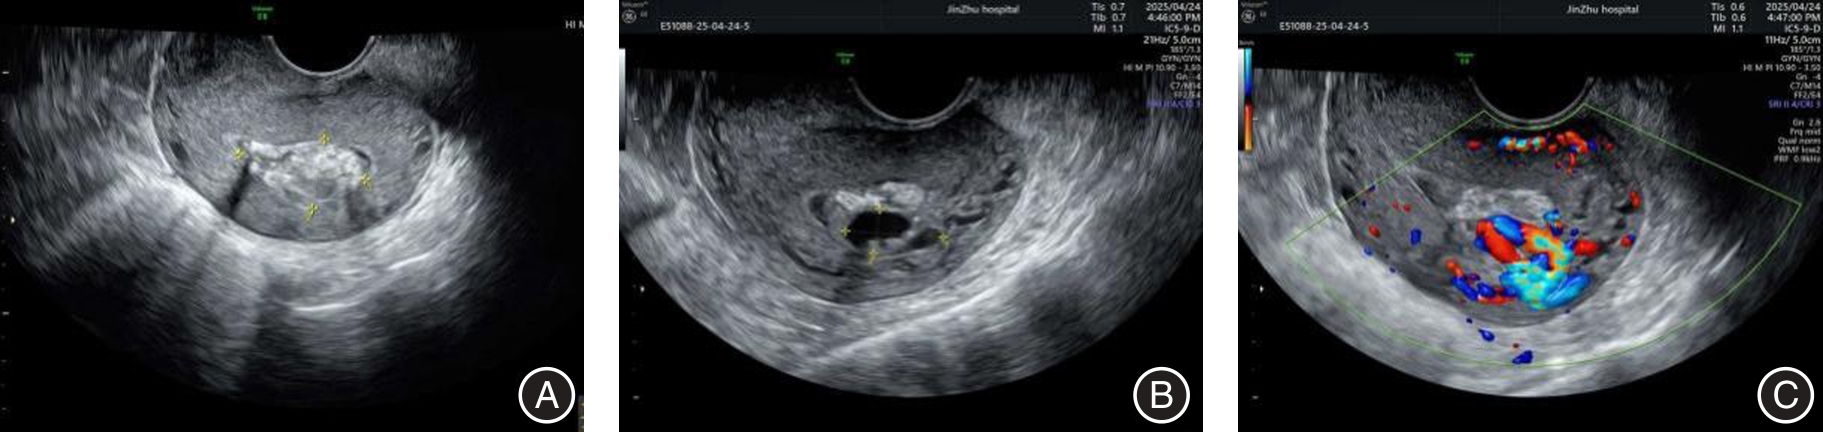

DEWILDE K, GROSZMANN Y, VAN SCHOUBROECK D, et al. Enhanced myometrial vascularity secondary to retained pregnancy tissue: Time to stop misusing the term arteriovenous malformation[J]. Ultrasound Obstet Gynecol, 2024, 63(1): 5-8. doi:10.1002/uog.27476 .

ERCOLINO C, FERRAZZI E, OSSOLA M W, et al. A comprehensive diagnostic approach to differentiate intrauterine arteriovenous malformation in cases of enhanced myometrial vascularity[J]. Arch Gynecol Obstet, 2024, 310(5): 2523-2529. doi:10.1007/s00404-024-07754-1 .

GREWAL K, AL-MEMAR M, FOURIE H, et al. Natural history of pregnancy-related enhanced myometrial vascularity following miscarriage[J]. Ultrasound Obstet Gynecol, 2020, 55(5): 676-682. doi:10.1002/uog.21872 .